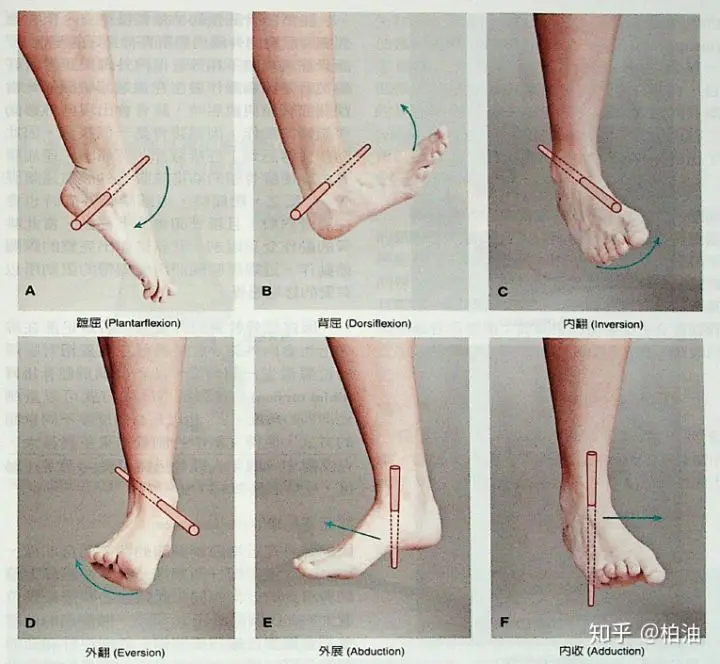

足踝的前后运动还在冠状面上,两个都是屈曲,往回勾脚尖为足背屈,往下踮脚尖为足跖屈。

足踝的前后运动还在冠状面上,两个都是屈曲,往回勾脚尖为足背屈,往下踮脚尖为足跖屈。

因为足踝的复杂结构不完全等同于其他关节,它的外展内收被定义为了外翻和内翻,水平旋转则被定义为了外展和内收。

足踝为了适应复杂多变的地形,它的运动方式不同于其他关节那样频繁进行屈、伸、展、收、旋这样单一方向的运动,而是以动作组合的形式出现,分为旋前(足背屈,外翻,外展)和旋后(足跖屈,内翻,内收)。

足踝为了适应复杂多变的地形,它的运动方式不同于其他关节那样频繁进行屈、伸、展、收、旋这样单一方向的运动,而是以动作组合的形式出现,分为旋前(足背屈,外翻,外展)和旋后(足跖屈,内翻,内收)。

步态中足旋前往往在落地承重或者即将承重时,因为旋前造成足弓松弛,足踝可以适应凹凸不平的地形。足旋后往往在离地或者即将离地的摆动期,此时因为足旋后造成足弓紧绷,力量向上传递以对身体进行推进。

过度的足旋前可以是外八字脚,足踝通过踝关节和距跟关节使整个足相对小腿做了一个包含了外旋的动作,所以足旋前时小腿相对的做了一个内旋,足旋后反之就是小腿相对足踝做了外旋。